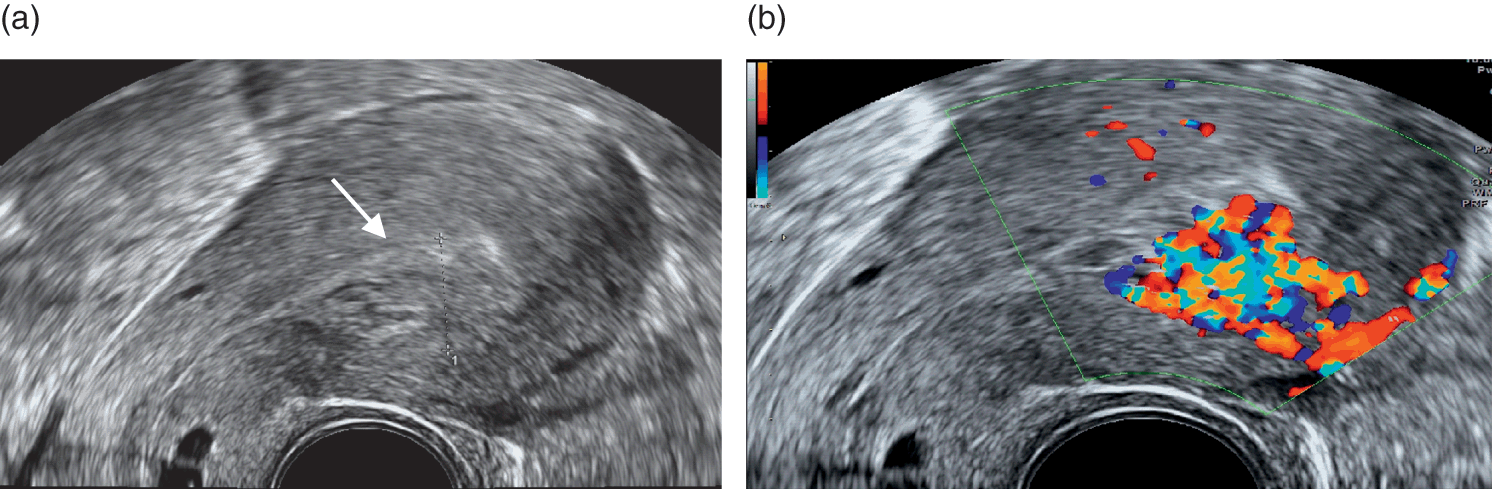

The Sonographic And Color Doppler Features Of Retained Products Of Conception Durfee 2005 Journal Of Ultrasound In Medicine Wiley Online Library